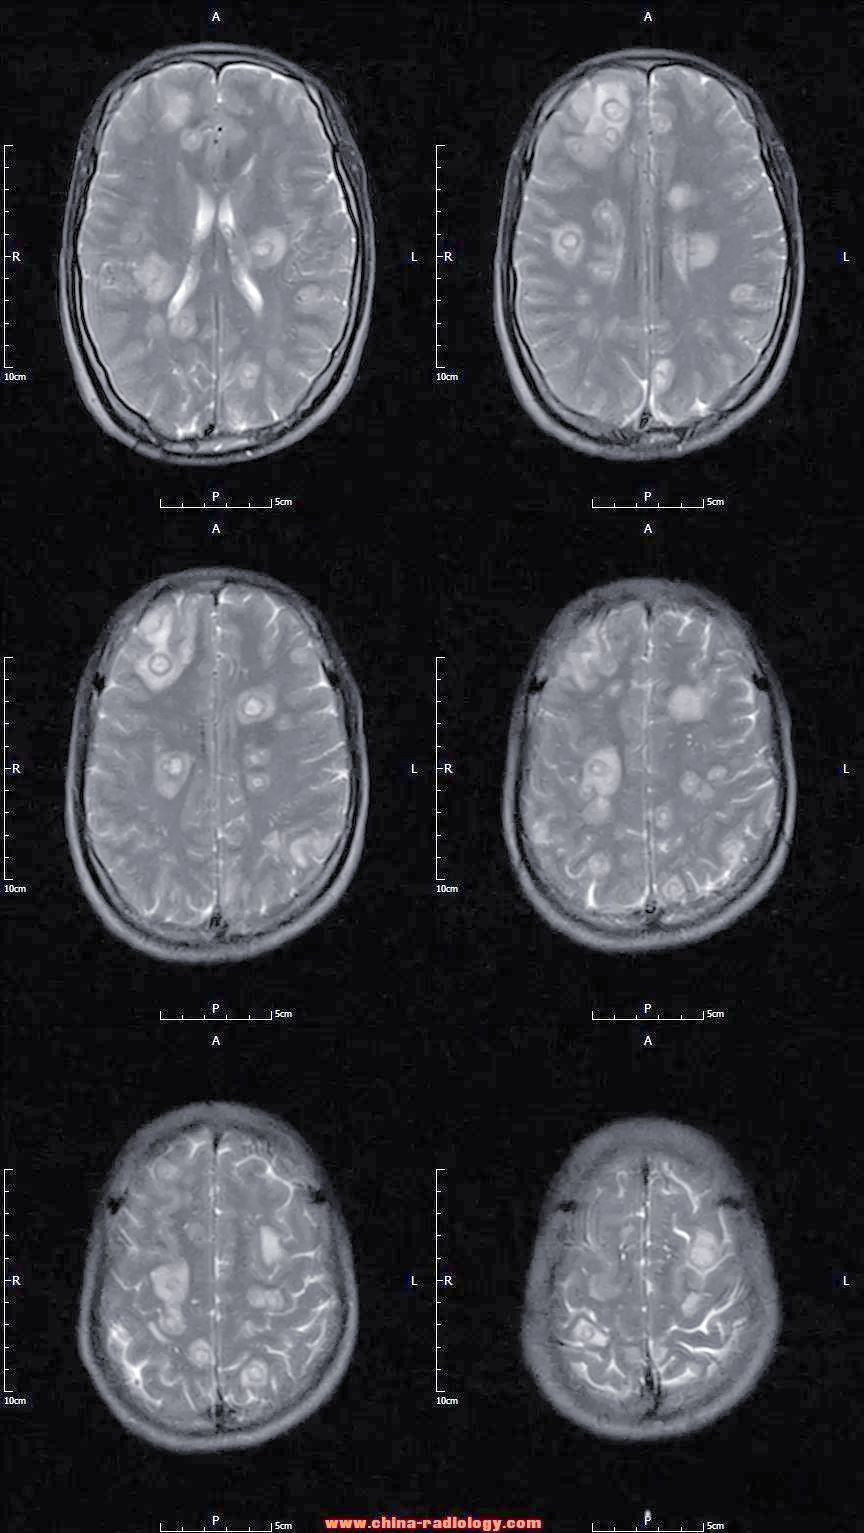

脑囊虫病

术语缩写脑囊虫病(neurocysticercosis,ncc)同义词囊虫病定义由猪肉

囊虫病:一种常见的中枢神经系统寄生虫感染